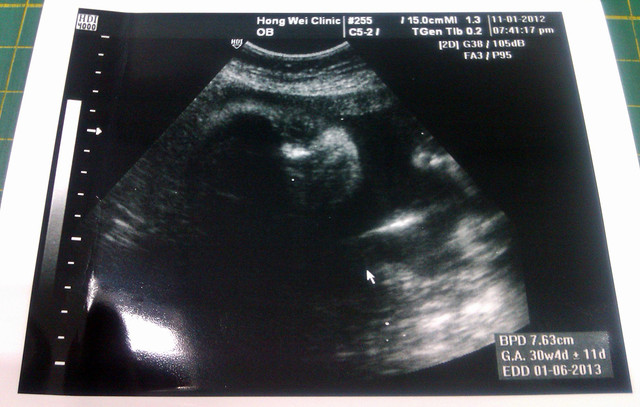

目前妞妞預估是30W+4D,重量約1700g,重量值比姐姐之前好一點![]()

而超音波的圖片,剛好拍到妞妞正在看我們耶...

圖片拿遠一點看應該就能看的滿清楚的吧![]()